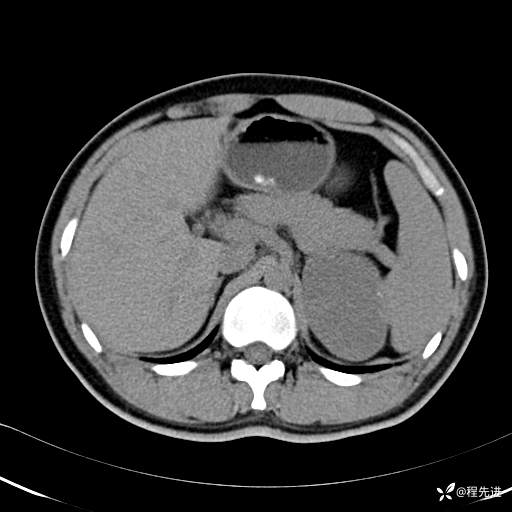

【腹盆】特别精彩病例|体检发现的左侧腹膜后占位期待您的精彩解读

患者年龄:25岁

简要病史:体检发现

CT平扫:(CT值:平扫,27HU,动脉期,27HU,门静脉期,31HU,平衡期,32HU)

CT增强:

门静脉期:

平衡期: